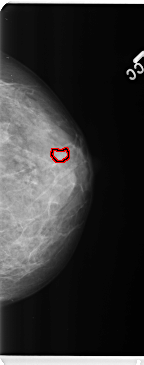

B_3359_1.LEFT_CC

LEFT_CC LINES 4736 PIXELS_PER_LINE 1872 BITS_PER_PIXEL 12 RESOLUTION 50 OVERLAY

FILE: B_3359_1.LEFT_CC.OVERLAY

TOTAL_ABNORMALITIES 1

ABNORMALITY 1

LESION_TYPE MASS SHAPE IRREGULAR MARGINS CIRCUMSCRIBED-OBSCURED

ASSESSMENT 4

SUBTLETY 3

PATHOLOGY BENIGN

TOTAL_OUTLINES 1

BOUNDARY